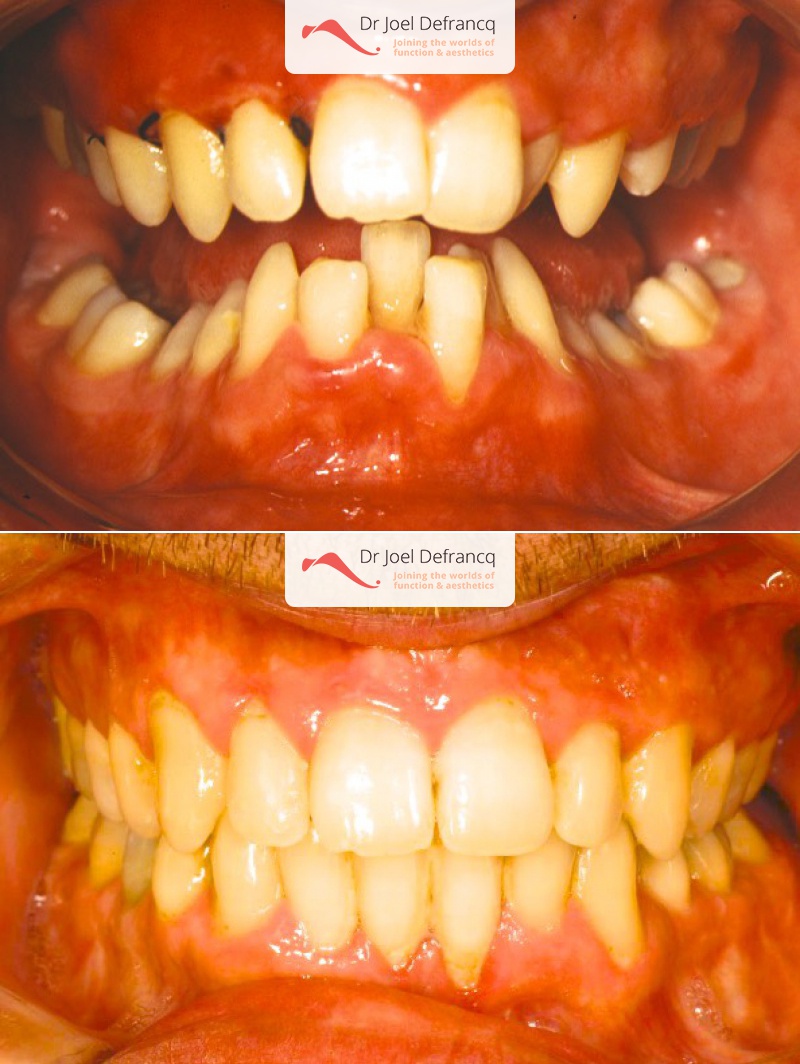

Kiro: Diepe beet, overbeet, diepe kin plooi

Diagnose van het gezicht

- Te kleine onderkaak (Overbeet)

- Te kort gezicht

Dentale diagnose

- Klasse II divisie 1

Kaakchirurgie

- Verlenging onderkaak (BSSO)

- Kinchirurgie